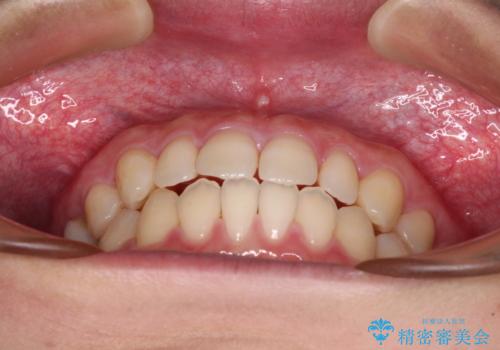

隙間だらけの歯列 インビザラインで改善

空隙歯列(すきっ歯)は、舌の突出癖をある程度改善できたとしても、後戻りにより隙間が開きやすいと言われています。

裏側から細いワイヤーで保定するとともに、睡眠時のマウスピース装着を徹底していただくことで、後戻りを最小限にとどめます。